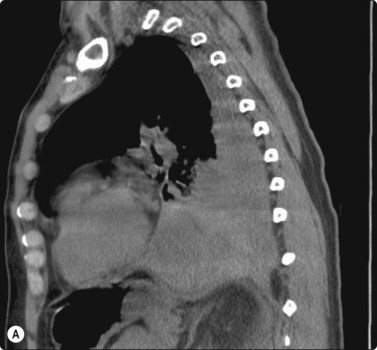

The most common sarcomas of this site include malignant fibrous histiocytoma and liposarcoma.131,132 Synovial sarcoma is well described.133 We have seen a single case of monophasic synovial sarcoma of mediastinum diagnosed on transoesophageal EUS FNB by the demonstration of SYT-SSX fusion transcripts by FISH on cell blocks, indicating X:18 translocation (all material shown here is courtesy of Dr. Anita Soma, PathWest QE II AP). (Fig. 9.10) The patient was a 45-year-old male with an 11-cm mass adjacent to the lower oesophagus, displacing the heart. Smears showed a rather bland spindle cell population but with mitotic activity. The cell block immunohistochemistry was negative for cytokeratins, CD117 and smooth muscle markers, making leiomyosarcoma and GIST unlikely. The tumor did show positive staining for CD99, BCL2 and CD34, raising the possibility of solitary fibrous tumor or synovial sarcoma. An SYT-SSX1 fusion transcript was detected by reverse transcriptase PCR, reinforcing the FISH cytogenetics. No other diagnostic procedures were undertaken (Fig 9.10).

image image image image image image image

Fig. 9.10 Synovial sarcoma

(A) Large infiltrative mass posterior to heart (Thoracic CT); (B) Loose fascicle of spindle cells including small blood vessels. Background of bare tumor nuclei (H&E, LP); (C) Loose cluster of bland spindle cells but with mitotic activity (H&E, HP); (D) Cell block, small spindle tumor cells with non-specific features (H&E, HP);(E) FISH on cell block, breakapart probe for SYT showing positive disruption of red-green-yellow components (FISH, HP); (F) FISH on cell block, fusion probe for SSX2 (green) and SYT (red) probes showing positive fusion of green and red components. (FISH, HP); (G) FISH on cell block, fusion probe for SSX2 (green) and SYT (red) probes showing positive fusion of green and red components (FISH, HP).